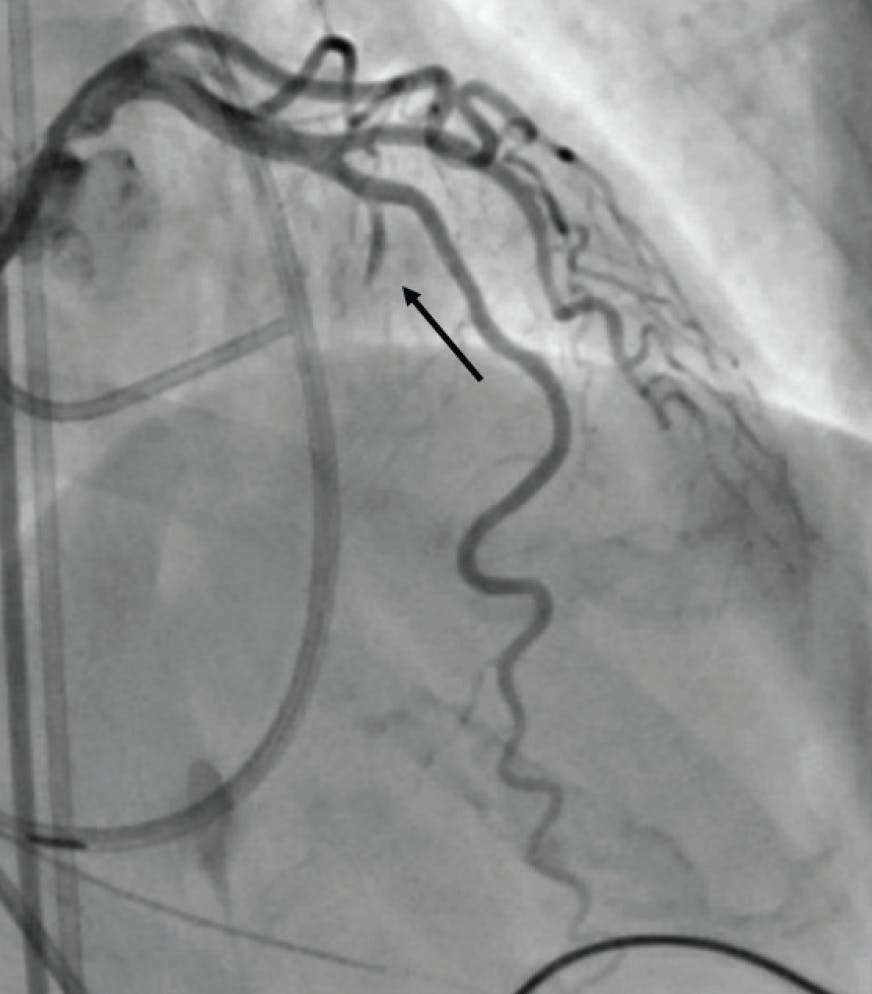

A careful review of the echocardiogram should confirm significant obstruction (> 50 mm Hg at rest or with provocation), systolic anterior motion (SAM) of the mitral valve, and “adequate” septal thickening (usually ≥ 1.5 mm). Most importantly, the septal anatomy requires careful review. The ideal anatomy is a proximal first septal perforator from the left anterior descending artery (LAD) that is about 1.5 mm in diameter and reaches not much farther than the midseptum (Figure 1). However, septal anatomy varies greatly, and some varieties are not suitable for ASA. For example, there may be an array of very small septals, or the proximal septals may be too small to instrument or unlikely to supply the correct place in the septum to eliminate obstruction (Figure 2). Alternatively, there may be a single, very large septal perforator that supplies a large amount of nontargeted myocardium (Figure 3). Note that septal perforators may arise from vessels other than the LAD, including the proximal diagonal, ramus, left main, and even right coronary arteries. The operator should review the baseline electrocardiogram. Because a right bundle branch block occurs in 40% of patients undergoing ASA, a pre-existing left bundle branch block is associated with a very high risk for permanent pacemaker.

Figure 3. Example of a large septal vessel supplying nearly the entire septum (arrow). This vessel could be used carefully if the proximal branch of this array is subselected.